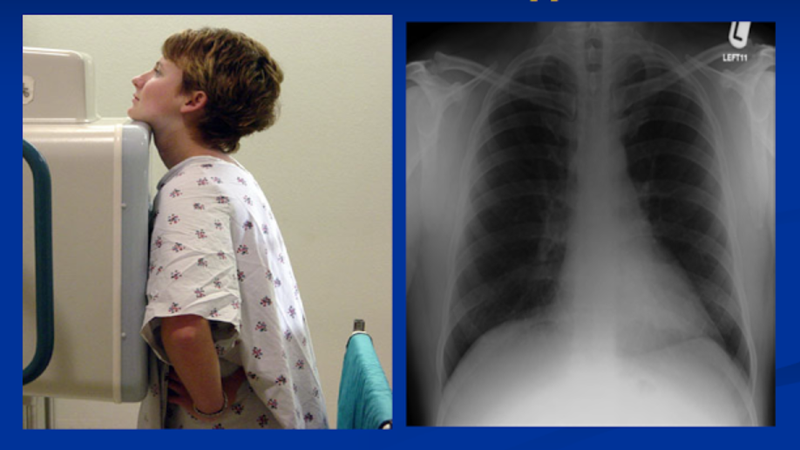

Cần hỏi bệnh và thăm khám kỹ các triệu chứng bệnh lao trước khi sàng lọc lao tiềm ẩn. Chụp X-quang ngực nếu nghi ngờ lao tiến triển. Bệnh nhân có triệu chứng lâm sàng và bất thường trên X-quang ngực cần được làm xét nghiệm thăm dò kỹ hơn để chẩn đoán lao tiến triển.

Chụp X-quang ngực nếu nghi ngờ lao tiến triểnCác phác đồ điều trị lao tiềm ẩn: